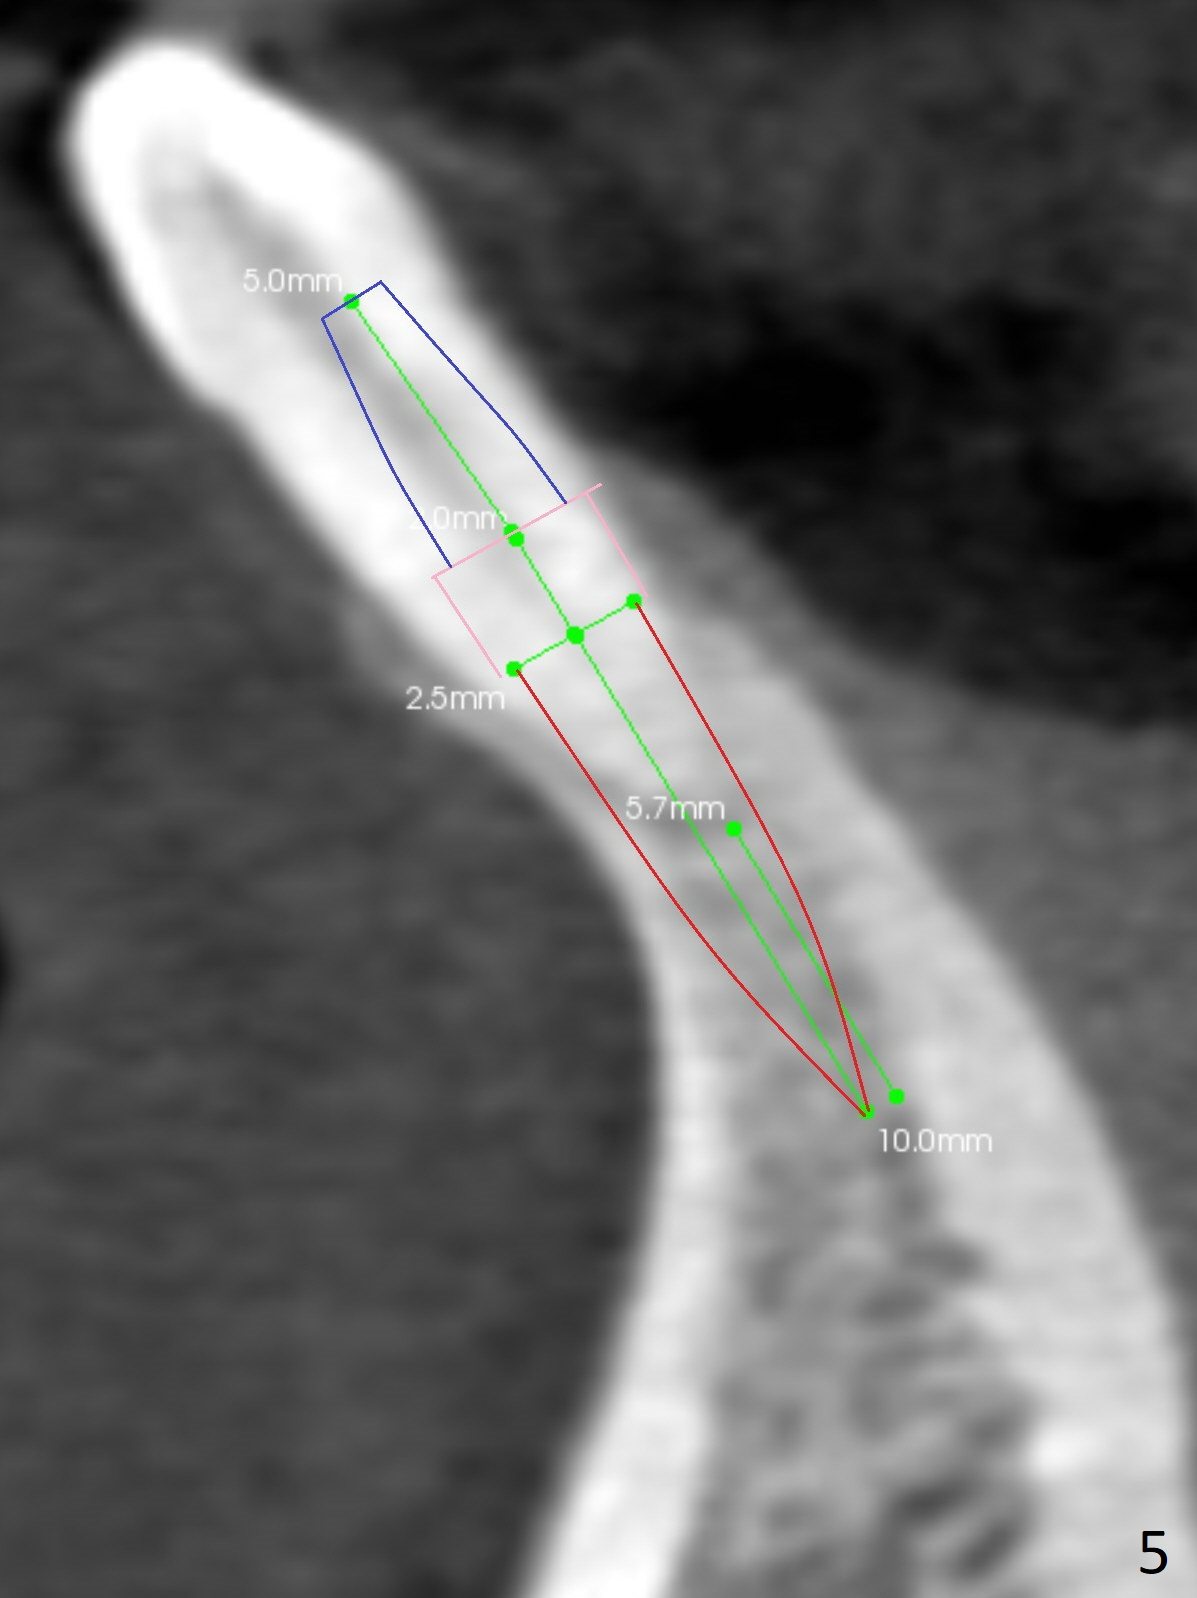

A 44-year-old woman has had bone loss at the tooth #25 for the last 4 years (Fig.1 *). Since the bone is narrow buccolingually (Fig.2 (CT coronal section)), a 1-piece implant with 2.5 mm in diameter is proper (Fig.3); but 12 mm in length makes the implant close to the lingual plate (Fig.2-4 L), with possible perforation. To avoid the latter, a shorter implant seems more appropriate for the site (Fig.5). Osteotomy is initiated in the apex with two fingers holding the buccolingual plates. Take PA preop. There is no buccal or lingual plate when the tooth is extracted; the socket bottom is flat buccolingually (Fig.6).